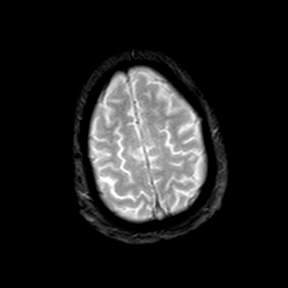

A 55 years old man with....